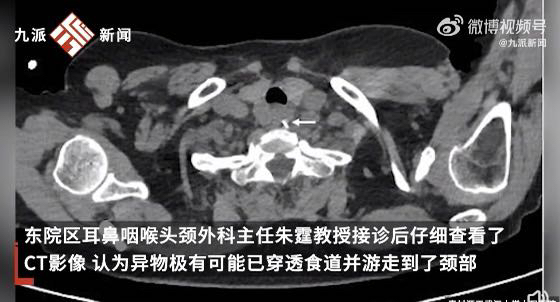

鱼刺卡喉后,吞饭团、噎馒头、喝醋……这些土办法轮番上阵的结果,很可能让鱼刺越卡越深,甚至危及生命。首先应马上停止进食,让周围人用手电筒照射咽部,初步查看。卡在较浅部位的细小鱼刺,可以试试用力咳嗽。一旦被鱼刺卡喉且自行无法咳出、取出,最安全有效的方法是立即就医,由耳鼻咽喉科医生检查后取出。